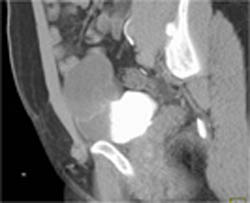

Saphenous Vein Graft Aneurysm